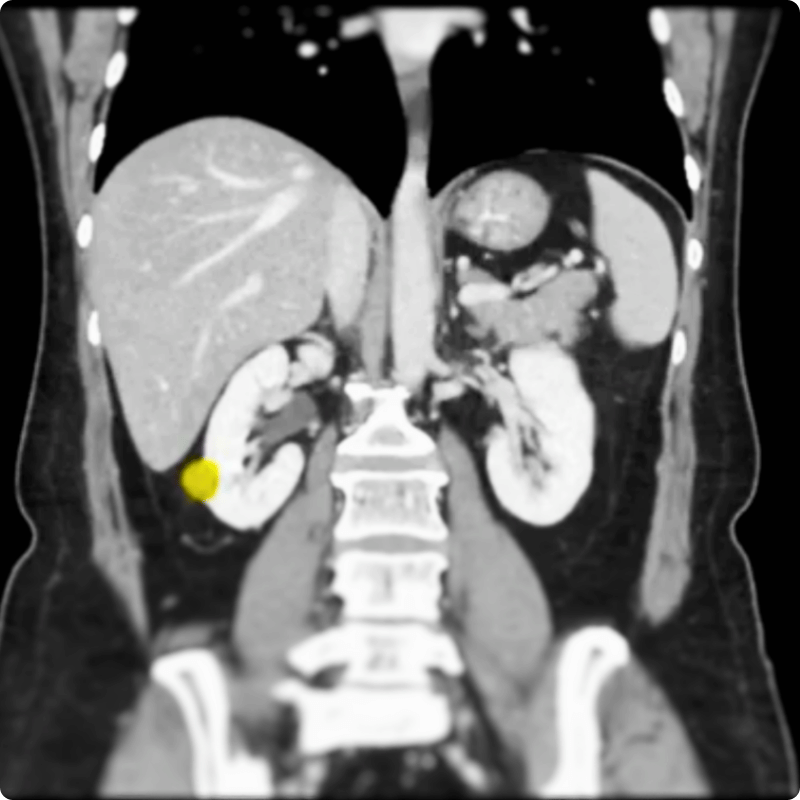

En lo que respecta a la nefrectomía parcial de puerto único para el cáncer de riñón, la Dra. Shirin Razdan es una autoridad reconocida en urología robótica. Con sede en Miami, se ha ganado la reputación de estar a la vanguardia de la cirugía renal mínimamente invasiva, ayudando a los pacientes a lograr excelentes resultados con tiempos de recuperación más cortos. En su último caso práctico quirúrgico, la Dra. Razdan demuestra la nefrectomía parcial de puerto único mediante acceso anterior bajo (AAL), un enfoque altamente refinado que combina precisión, eficiencia y comodidad para el paciente. Este video ofrece una mirada excepcional tras bambalinas sobre cómo las técnicas robóticas de vanguardia están transformando la cirugía del cáncer de riñón.Qué demuestra el video

En este caso quirúrgico paso a paso, el Dr. Razdan muestra cómo se realiza una nefrectomía parcial de puerto único mediante la técnica de acceso anterior bajo con una plataforma robótica de puerto único:- Posicionamiento del paciente y planificación de la incisión: estableciendo un punto de entrada anterior bajo para un acceso óptimo.

- Resección precisa del tumor: utilizando herramientas robóticas avanzadas para extirpar la porción enferma del riñón, conservando al mismo tiempo el tejido sano.

- Flexibilidad para diferentes localizaciones tumorales: adecuado para tumores renales anteriores, posteriores e incluso complejos.